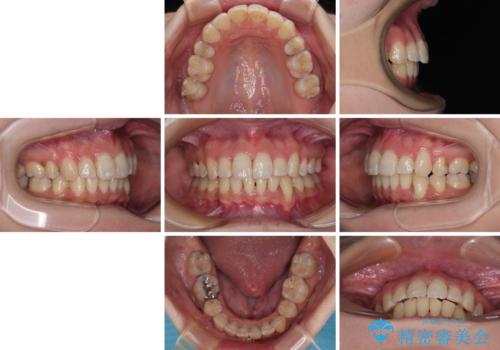

出っ歯を治したい ワイヤー装置での抜歯矯正で劇的変化!

- 口元がひどく突出するくらいの上顎前突を気にして来院された患者様です。

舌の突出癖が顕著で、上顎歯列は完全なV字型となっている状態でした。

下顎歯列にも八重歯があり、上下左右の第一小臼歯4本を抜歯して、ワイヤー装置にて矯正治療を行うこととしました。

どこまで口元の突出感を改善できるのか不安でしたが、舌のトレーニングをしっかりと行ってくださり、我々も驚くほど劇的に改善することができました。